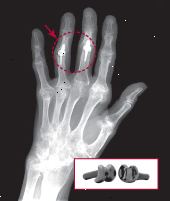

Η ακτινογραφία δείχνει το χέρι ενός 57-year-old γυναίκα με οστεοαρθρίτιδα. Το δεύτερο αρθρώσεις του μεσαίου δακτύλου και του παράμεσου έχουν λάβει τεχνητό εγγύς αρθρώσεις μεσοφαλαγγικές από πυράνθρακας (ένθετο φωτογραφία). X-ray ανατυπώνεται με την άδεια, Barry P. Simmons, MD? Ένθετο φωτογραφία είναι ευγενική προσφορά της Αναλήψεως Ορθωτική |

Όπως και με τις αρθρώσεις MCP, οι χειρουργοί έχουν χρησιμοποιήσει τόσο σιλικόνη και πυράνθρακας να αντικαταστήσει το εγγύς άρθρωση μεσοφαλαγγικές, το δεύτερο ή μεσαία άρθρωση του δακτύλου (βλέπε ακτίνες Χ). Αυτές οι αρθρώσεις είναι καλοί υποψήφιοι για την αντικατάσταση, διότι από κοινού σύντηξη, ιδίως από το δαχτυλίδι και τα μικρά δάχτυλα, μπορεί να είναι δύσκολο να πιάσει τα αντικείμενα. Μια μελέτη του 2007 στο περιοδικό Journal of Χειρουργικής Χεριού διαπίστωσε ότι οι δύο τύποι των εμφυτευμάτων απέδωσαν εξίσου καλά στην ανακούφιση του πόνου και τη βελτίωση του εύρους κίνησης. Ανάκαμψη από αυτές τις χειρουργικές επεμβάσεις διαρκεί περίπου όσο αναρρώνει από τον καρπό-αντικατάσταση της άρθρωσης.